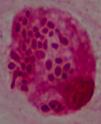

Diagnóstico y evoluciónLa serología para VIH resulta positiva, con carga viral por PCR de 107.000 copias ARN/ml y recuento de CD4 total de 11 cels/μL. Los hemocultivos para microorganismos comunes y micobacterias resultan negativos, cultivos en heces y orina para micobacterias negativos, ELI-SPOT (antígenos ESAT-6 y CFP-10) y Mantoux negativos, VDRL y antígeno de C. neoformans negativos. Del lavado broncoalveolar resultan negativos los cultivos para microorganismos comunes, PCR para micobacterias, antígenos y PCR para CMV, VEB, VHS-1 y 2 y virus respiratorios. En el examen directo con tinción de Gram de la muestra de esputo se observan abundantes levaduras (fig. 2). El LBA se prepara por citocentrifugación y se realiza tinción de plata, que descarta la presencia de P. jirovecii, tinción Giemsa para recuento celular y tinción de Gram. En todos los casos se observa la presencia de levaduras intracelulares, en algunos casos con gemación, que presentan un halo de exclusión (fig. 3). La morfología de la levadura sugiere la posibilidad de histoplasmosis, microorganismo clasificado en el nivel de peligrosidad 3, por lo que se procedió según las recomendaciones de la Sociedad Española de Microbiología Clínica1. El personal del laboratorio que pudiera entrar en contacto con muestras y cultivos de este paciente fue advertido e informado de las medidas de precaución adicionales que se tomaban. Todos los procedimientos posteriores, excepto los de biología molecular a partir de la extracción de ADN, fueron realizados en un laboratorio de nivel de contención 3. Al completar el estudio los cultivos fueron destruidos. Se inicia la identificación de esta levadura por métodos moleculares.